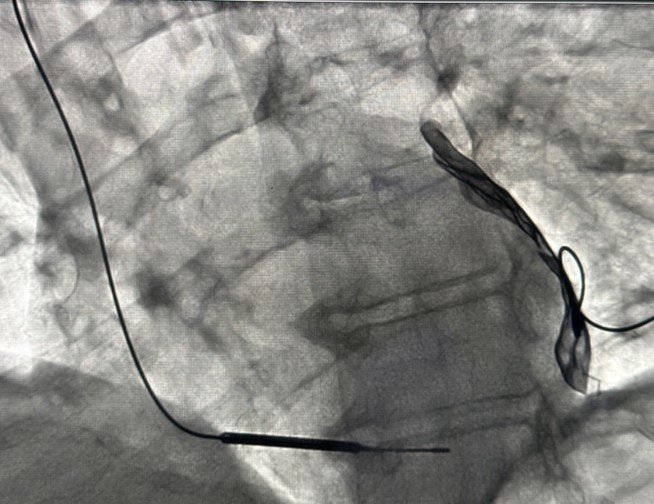

U sklopu međunarodnog projekta u Kliničkom centru Univerziteta u Sarajevu 58 godišnjem pacijentu ugrađen je uređaj za mikrostrujnu terapiju srca (Cardiac Microcurrent Therapy System C-MIC-II). Ovo je prvi put u historiji KCUS da je urađena ugradnja ovakvog uređaja.

Uloga ovog aparata je da kontinuiranom mikrostrujom određene frekvencije, poveća srčanu snagu i dovede do poboljšanja srčane funkcije.

ilustracija C-MIC-II uređaja radiografski prikaz C-MIC-II uređaja izvor – KCUS